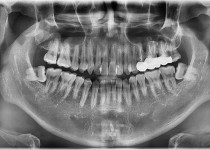

만 75세 상악 풀아치 증례